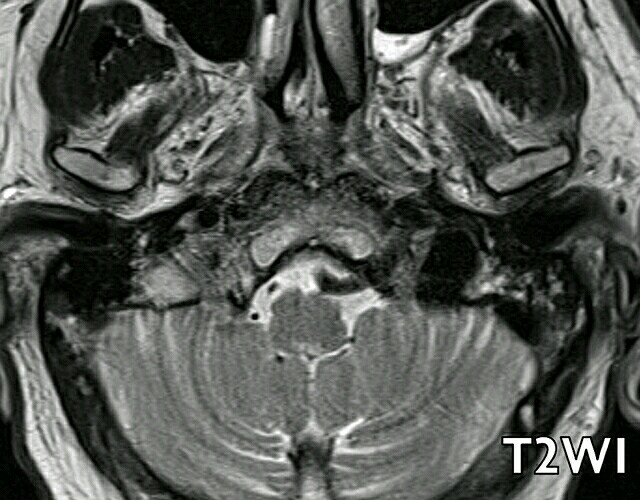

患者男性,71 岁,有帕金森综合征。 结合上图,考虑如何诊断?